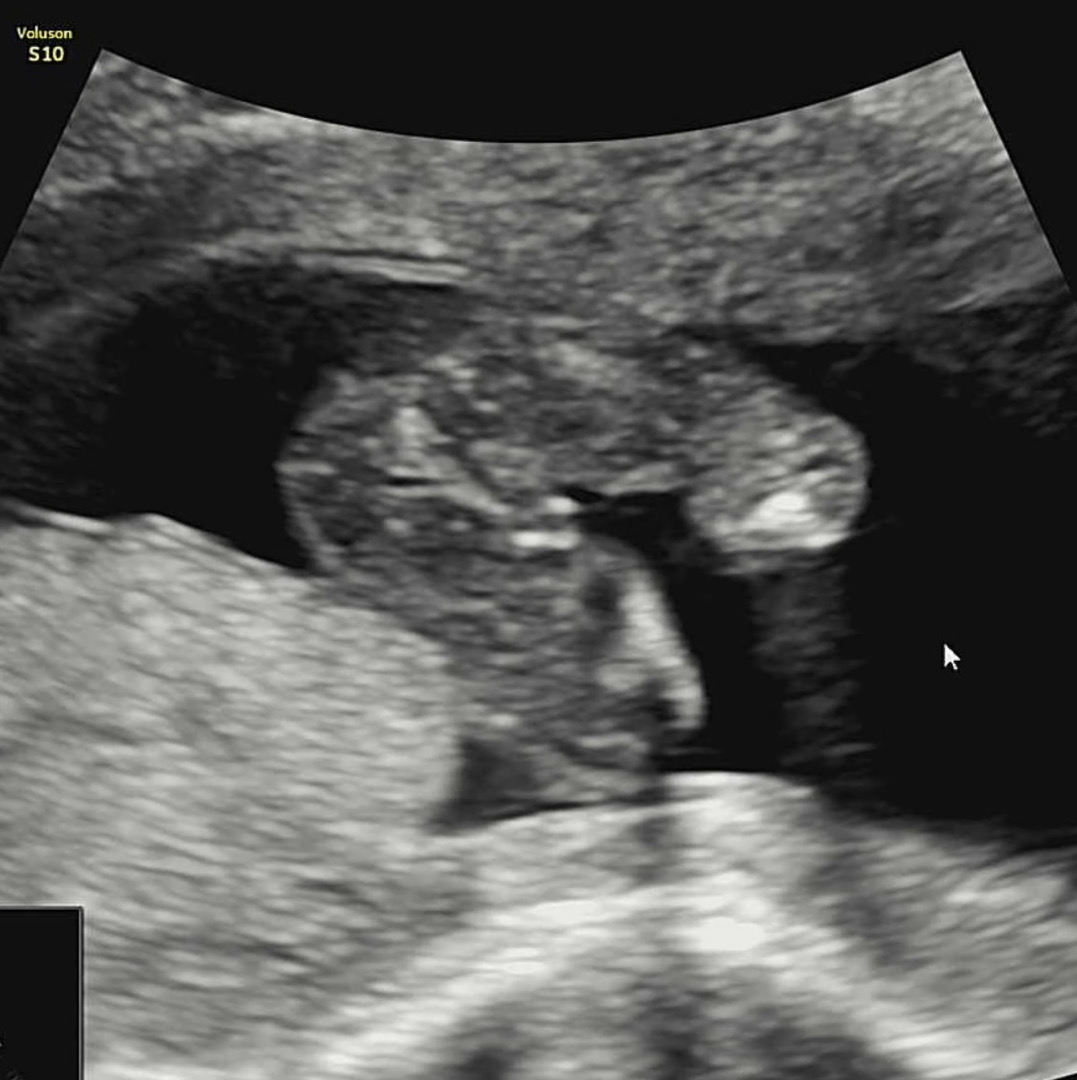

16주 초음파 봐주세용!!!!!!!

16주 2일 초음파 보고왔는데 의사쌤이 100% 아들같다고 하셨는데..반전 없을까여..?ㅎㅎ